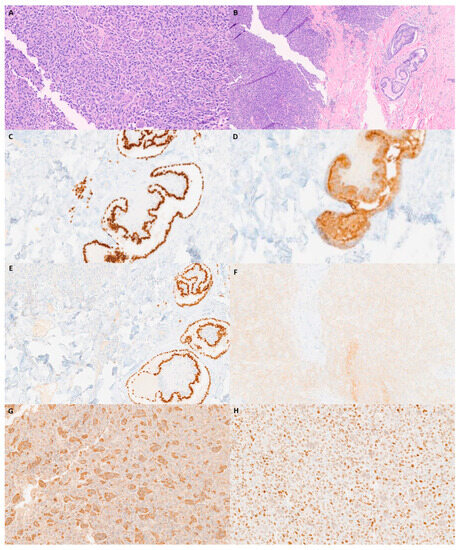

The skin lesion was biopsied. Two separate components were microscopically identified: a rare glandular focus (Figure 2A) and a second poorly differentiated component (Figure 2B). The glandular focus was papillary and positive for AE1/AE3, TTF1, and PAX8 (Figure 2C–E). CD68 was positive in scattered giant cells in the poorly differentiated focus (Figure 2F). Since a thyroid gland was absent, an anaplastic thyroid carcinoma caused by ectopic thyroid was the main differential diagnosis. Ectopic thyroid is a developmental abnormality where the thyroid gland fails to migrate from the primitive foregut floor to the anterior neck. Ectopic thyroid may result in hypothyroidism, hyperthyroidism, or no clinical symptoms [1]. Ectopic thyroid tissue developing malignancy is relatively rare, occurring in less than 1% of cases [2]. Multiple termini have been reported, including the lateral side of the neck, the sternocleidomastoid muscle, and the tongue. The most common ectopic cancer type is papillary thyroid carcinoma, which is consistent with the prevalence of papillary thyroid carcinoma in the thyroid [3,4,5]. An excisional biopsy of the mediastinal mass was performed to confirm the diagnosis.

Figure 2.

Microscopic and immunohistochemical examination of skin biopsy. (A) H&E-staining (40×) image with foci of papillary and multinucleated giant-cell neoplasms. (B) Higher-power H&E-staining image (100×) of poorly differentiated neoplasm foci. (C) AE1/AE3 (40×). (D) CD68 (40×). (E) TTF-1 (40×). (F) PAX-8 (40×).

The carcinoma’s histopathology consisted primarily of a poorly differentiated tumor with abundant giant cells. Rare minute papillary foci were identified in addition to a poorly differentiated component on the single frozen section slide (Figure 3A,B). TTF1, thyroglobulin, PAX8, and BRAF V600E were all positive (Figure 3C–F). SATB2 and CD68 were positive in scattered giant cells (Figure 3G,H). A diagnosis of anaplastic thyroid carcinoma with giant cells was made. Anaplastic thyroid carcinoma is a relatively uncommon carcinoma. The corresponding prognosis is very poor, with an average median relative survival of 3 to 6 months [6]. Histologically, anaplastic thyroid carcinoma may present with multiple histomorphological variants, such as pleomorphic, epithelioid, spindle cell, rhabdoid, osteoclast giant-cell-rich, and squamous cell carcinoma [7]. Due to its variable morphological presentation, immunohistochemistry is required for diagnosis. The literature reports strong staining results with AE1/AE3, CAM5.2, P53, and PAX-8 positivity in 36% of cases. TTF-1 and thyroglobulin, thyroid lineage markers, are usually negative [8]. Giant-cell-rich anaplastic thyroid carcinoma is a rare pattern within the anaplastic thyroid carcinoma morphological spectrum, with only a few cases reported in the literature. Histologically, numerous osteoclast giant cells with multiple nuclei and elevated mitotic activity have been reported [9]. The corresponding immunohistochemical staining patterns are like those of other types of anaplastic thyroid carcinoma with a negative expression of TTF-1 and thyroglobulin. Common mutations in anaplastic thyroid carcinoma include TERT promoter mutation (73%), TP53 (59%), BRAF (29%), and RAS (23%) [10]. Additional immunohistochemical staining procedures were performed to exclude other entities in the differential diagnosis, such as sarcomatoid carcinoma of the lung, prostate carcinoma, colon carcinoma, leiomyosarcoma, rhabdomyosarcoma, melanoma, dedifferentiated liposarcoma, angiosarcoma, myeloid sarcoma, and follicular dendritic cell sarcoma.

Figure 3.

Microscopic and immunohistochemical examination of the sternal mass. (A) H&E (100×). (B) H&E with thyroid papillary foci (40×). (C) TTF-1 at papillary foci (100×). (D) Thyroglobulin in anaplastic tumor cells (100×). (E) PAX-8 in anaplastic tumor cells (100×). (F) BRAF V600E (100×). (G) CD 68 (100×). (H) SATB2 (100×).